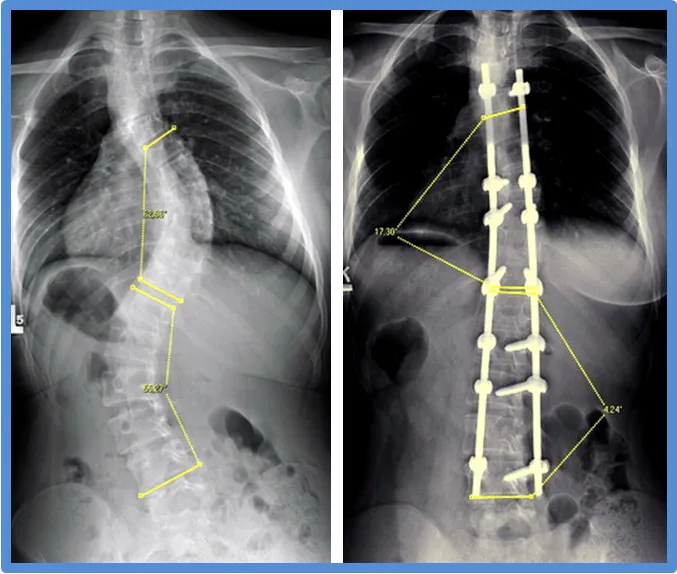

Kąt Cobba, czyli kluczowa liczba decydująca o długości leczenia

Kąt Cobba to podstawowy miernik, który pozwala nam określić stopień zaawansowania skoliozy. Jego wartość, ustalana na podstawie zdjęć rentgenowskich, jest dla mnie i innych specjalistów kluczową informacją, która bezpośrednio wpływa na wybór metody leczenia i przewidywany czas trwania rehabilitacji. Im większy kąt Cobba, tym zazwyczaj bardziej intensywna i dłuższa terapia jest potrzebna. To od tej liczby zależy, czy zastosujemy jedynie fizjoterapię, wdrożymy leczenie gorsetowe, czy też rozważymy interwencję chirurgiczną.

W przypadku skoliozy III stopnia, czyli gdy kąt Cobba przekracza 40-50 stopni i wada postępuje, leczenie chirurgiczne staje się często koniecznością. Operacja ma na celu trwałą korekcję skrzywienia i stabilizację kręgosłupa. Jednak sam zabieg to dopiero początek drogi. Rehabilitacja pooperacyjna jest absolutnie kluczowa dla pełnego powrotu do sprawności i komfortowego funkcjonowania w życiu codziennym. Bez niej, nawet najlepiej przeprowadzona operacja nie przyniesie oczekiwanych rezultatów.

Całkowita rehabilitacja pooperacyjna trwa średnio od 3 do 12 miesięcy, choć w niektórych przypadkach może się nieco wydłużyć. W tym okresie skupiamy się na kilku kluczowych celach. Początkowo jest to wzmacnianie mięśni głębokich tułowia i stabilizatorów kręgosłupa, które zostały osłabione lub naruszone podczas operacji. Następnie pracujemy nad poprawą zakresu ruchu, co jest ważne, mimo usztywnienia kręgosłupa. Kolejnym etapem jest przywrócenie prawidłowych wzorców ruchowych, nauka ergonomii i adaptacja do nowej postawy. To intensywny czas, który wymaga cierpliwości i systematyczności.